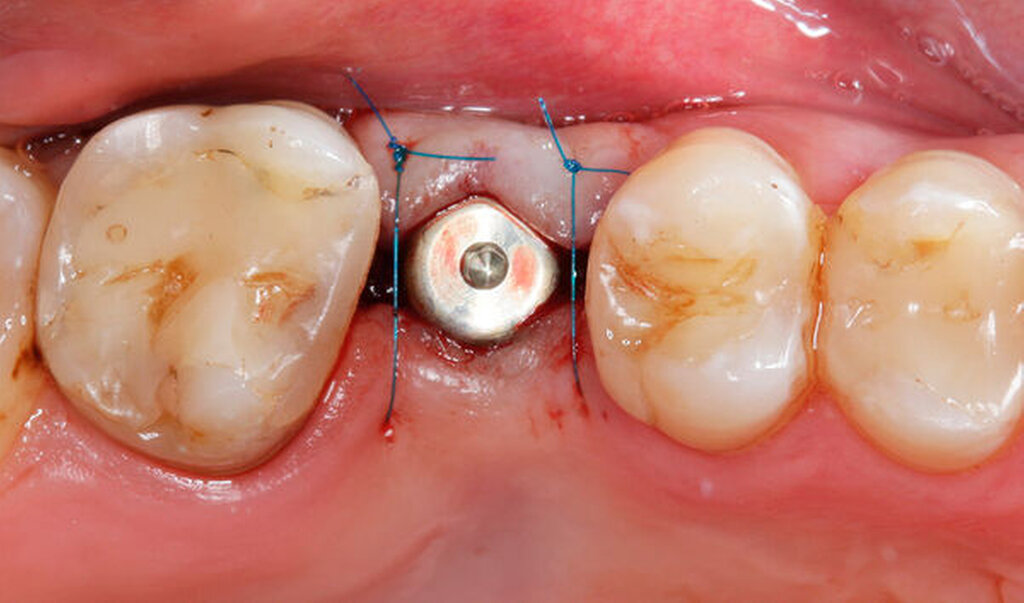

Im vorliegenden Patientenfall erfolgte die Freilegung drei Monate nach der Implantatinsertion mit einer leicht nach palatinal versetzten, krestalen Inzision in Ausdehnung bis zu den Nachbarzähnen. Dadurch wurde unter Verwendung eines konfektionierten Gingivaformers die Schleimhaut zur Verbesserung des vestibulären Defizits leicht nach bukkal verschoben. Die Fixation des Lappens erfolgte mit einer mesialen und einer distalen Einzelknopfnaht (Prolene 6–0, Ethicon Inc., Raritan, USA, Abbildung 6).